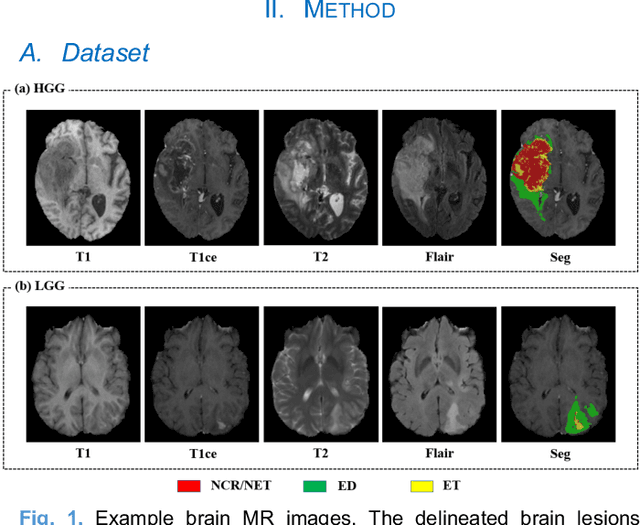

Abstract:Radiomics and deep learning have shown high popularity in automatic glioma grading. Radiomics can extract hand-crafted features that quantitatively describe the expert knowledge of glioma grades, and deep learning is powerful in extracting a large number of high-throughput features that facilitate the final classification. However, the performance of existing methods can still be improved as their complementary strengths have not been sufficiently investigated and integrated. Furthermore, lesion maps are usually needed for the final prediction at the testing phase, which is very troublesome. In this paper, we propose an expert knowledge-guided geometric representation learning (ENROL) framework . Geometric manifolds of hand-crafted features and learned features are constructed to mine the implicit relationship between deep learning and radiomics, and therefore to dig mutual consent and essential representation for the glioma grades. With a specially designed manifold discrepancy measurement, the grading model can exploit the input image data and expert knowledge more effectively in the training phase and get rid of the requirement of lesion segmentation maps at the testing phase. The proposed framework is flexible regarding deep learning architectures to be utilized. Three different architectures have been evaluated and five models have been compared, which show that our framework can always generate promising results.